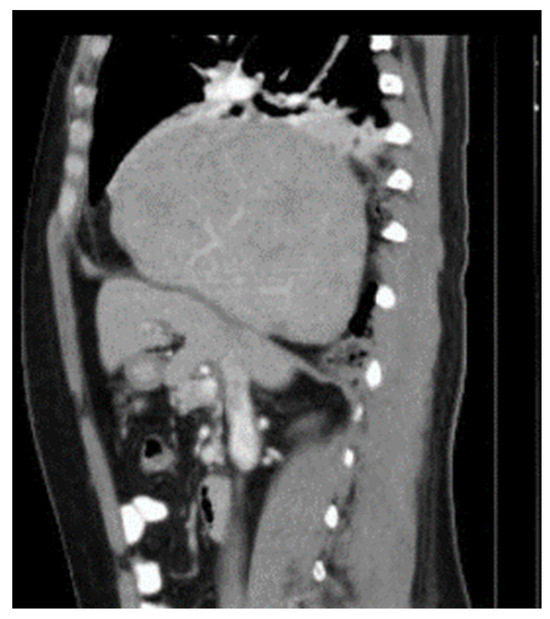

Diaphragmatic Liver Herniation after Radiofrequency Ablation of a Secondary Liver Tumor